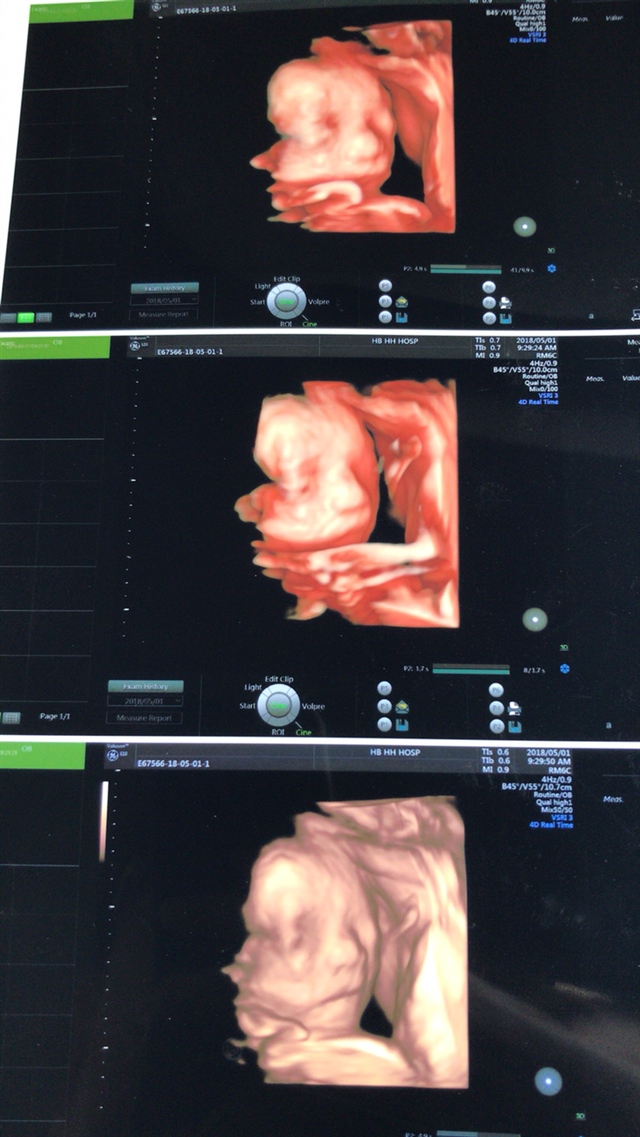

产前检查 B超